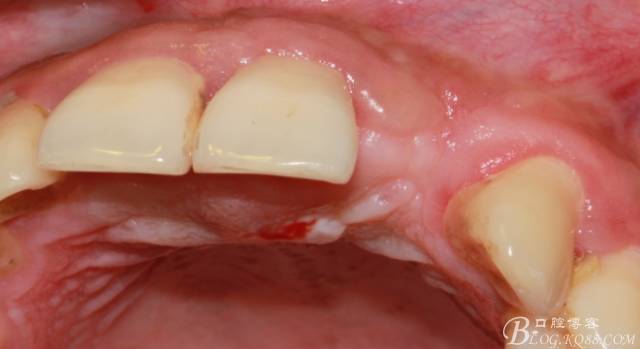

4個(gè)月后,唇側(cè)豐滿度尚可,與鄰牙之間齦乳頭完整。

保留齦乳頭翻小瓣。